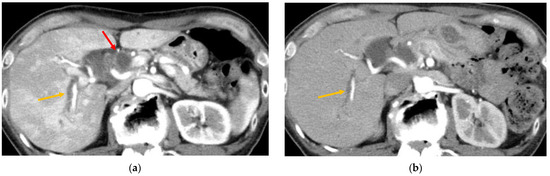

2.2.3. Radiology Images